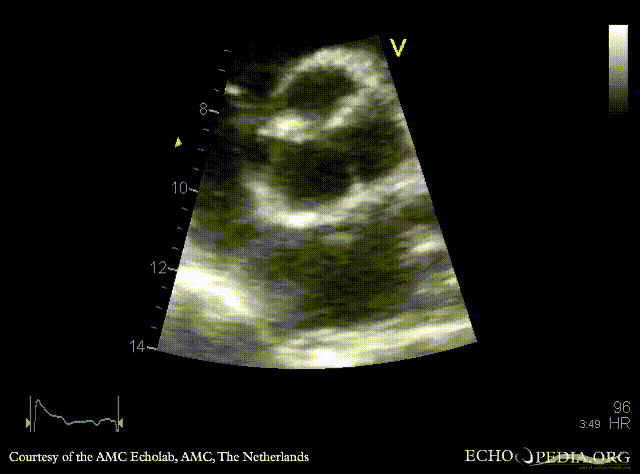

Endocarditis of aortic valve

PLAX: vegetations on aortic valve PSAX: thickend bicuspid aortic valve